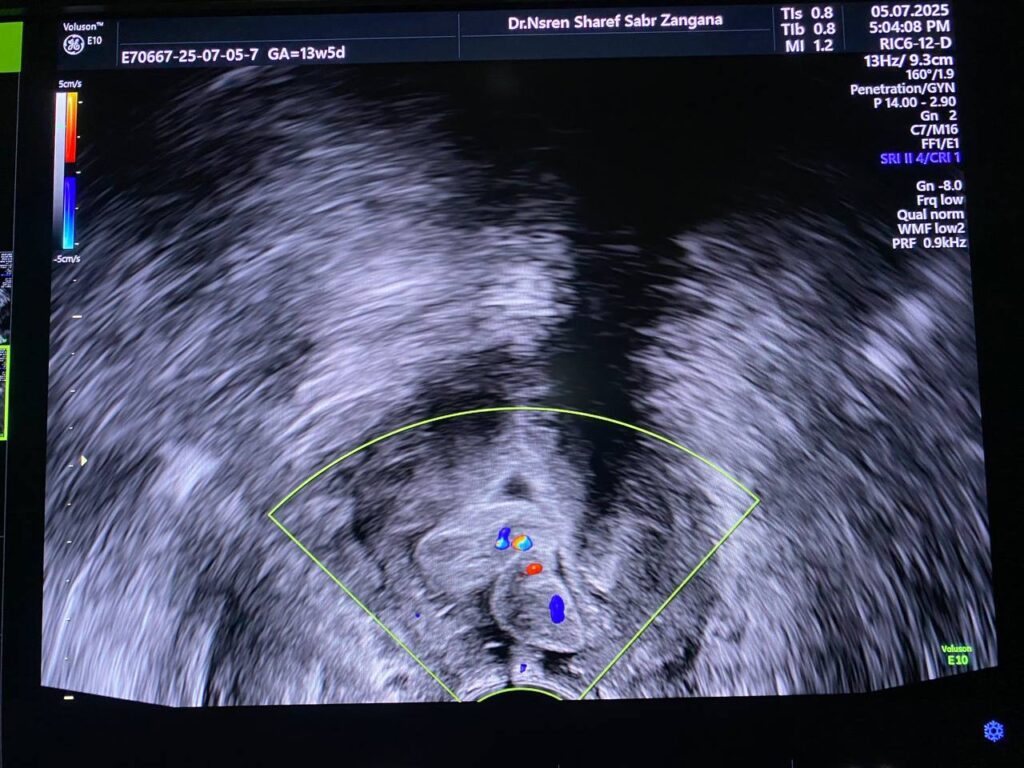

Presence of isoechoic vascular mass 23x6x25mm within the cervical canal , mostly polyp , please for further study to exclude other pathology .

Presence of isoechoic vascular mass 23x6x25mm within the cervical canal , mostly polyp , please for further study to exclude other pathology .